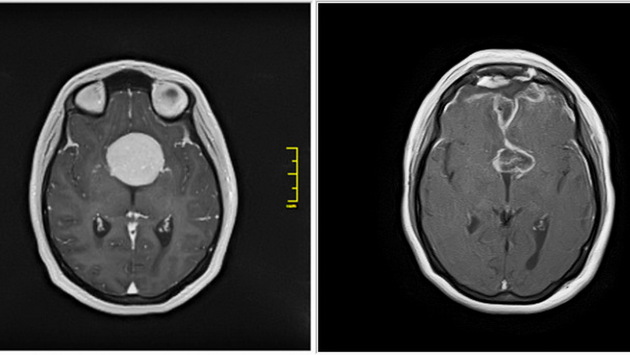

Как сообщает пресс-служба НИИТО, пропадать зрение у пациентки начало после родов в 2016 году. Тогда хуже стал видеть левый глаз. Лечение у офтальмолога не помогало, и постепенно зрение терялось и на правом глазу. Тогда женщина сделала МРТ и выяснила, что у нее в голове гигантская опухоль — менингиома турецкого седла — которая сдавливает и разрушает ее зрительные нервы и обрастает сонные артерии.

Из-за того, что на родине Кристине не смогли помочь, она воспользовалась услугами НИИТО, так как здешняя нейрохирургическая клиника имеет большой опыт в сфере нейроонкологии. В январе 2021 года хирурги НИИТО успешно удалили опухоль.

«Послеоперационный период у Кристины Овсепян протекал гладко. Пациентка выписана в удовлетворительном состоянии под наблюдение невролога по месту жительства. Уже на момент выписки Кристина отмечала улучшение состояния, и мы надеемся, что зрение значительно улучшится в ближайшем будущем», — говорит оперировавший женщину начальник научно-исследовательского отделения нейрохирургии, врач-нейрохирург высшей категории Вячеслав Ступак.